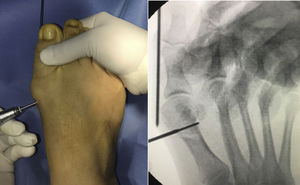

Modified bösch osteotomy surgical techniqueUnder the same conditions as described above, in the Bösch osteotomy using a medial approach, a straight cut is made parallel to the distal joint veneer of the metatarsal at neck level. The wire is advanced in the same way as in the chevron osteotomy in the medullary canal for lateral cephalic displacement.

It is fixed with a screw from proximal towards the head and from medial to lateral, and the K-wire is maintained (Fig. 2). Percutaneous release of the hallux adductor tendon is performed.

Walking in a post-operative shoe with immediate weightbearing is also allowed. Weekly dressings are prescribed and the Kirschner wire is removed in the clinic in the third post-operative week (Figs. 3 and 4).